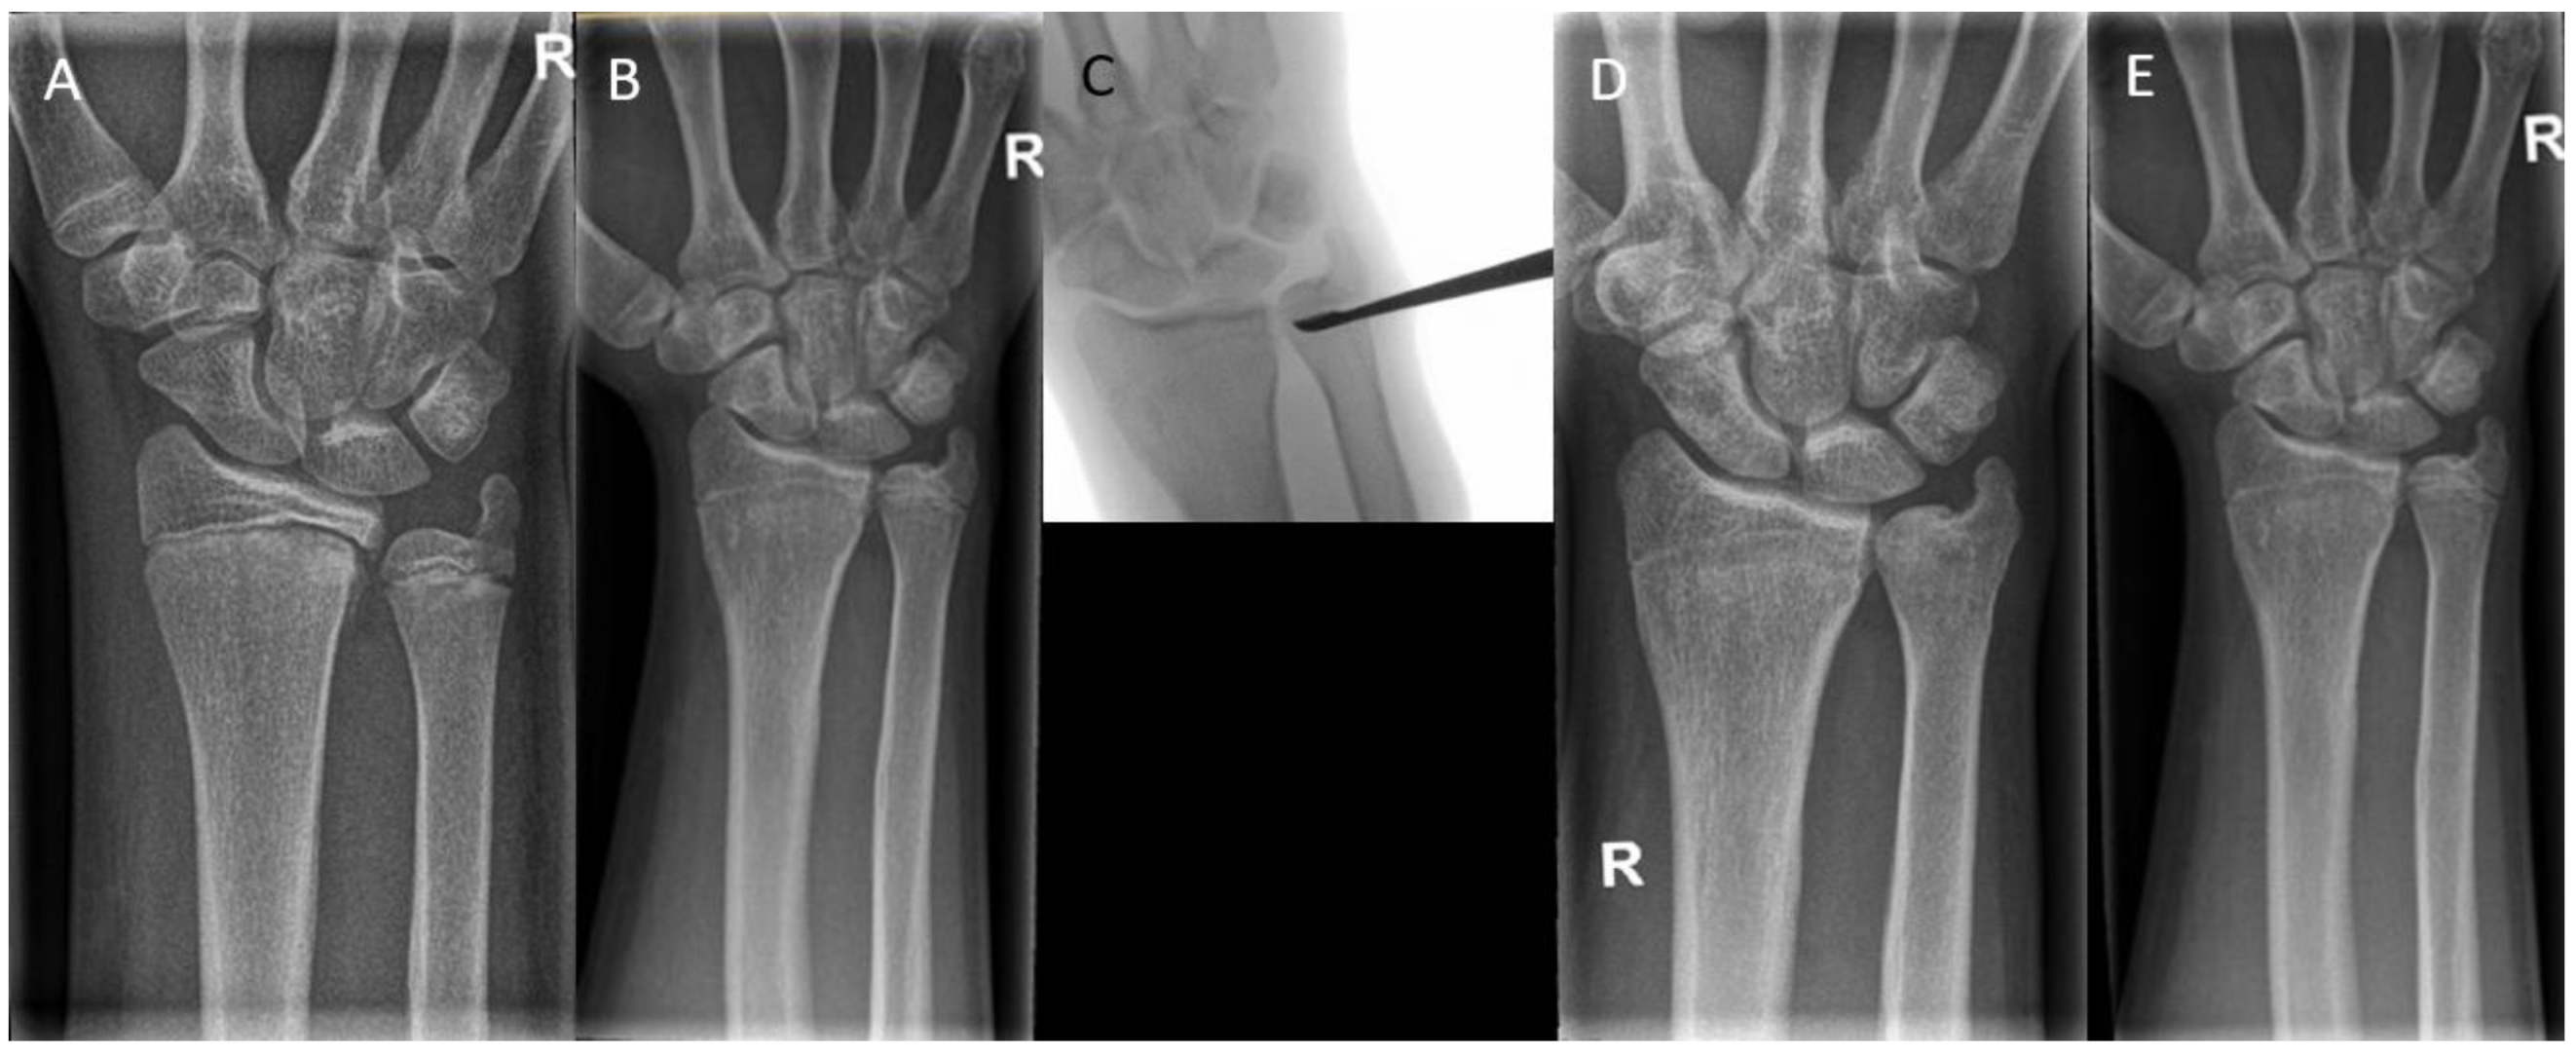

Figure 8. (A) A 15-year-old boy with premature closure of the distal radial physis after a Salter–Harris type 2/4 fracture. Initially, the boy had an ulna minus wrist. (B) A closed radial physis, accompanied by an impending ulna plus. (C) Intraoperative radiographs during epiphysiodesis of the ulna. (D) Postoperative radiographs show a closed physis of both the radius and the ulna. Note that the ulna had been growing until the epiphysiodesis, leading to an ulna zero. (E) Radiographs after 1-year follow-up. Note the unaltered ulnar variance.

6.3. Complete Epiphysiodesis

In complete epiphysiodesis, the physis is completely removed or temporarily tethered across the entire width. This procedure is performed to prevent overgrowth. Surgical options range from percutaneous techniques using drills and curettes to more invasive open techniques. For example, premature closure of the distal radial physis can be associated with ulnar overgrowth, leading to altered wrist mechanics and pain. An epiphysiodesis of the ulna can prevent worsening of the deformity (Figure 8).

Scheider et al. [49] reported seven cases with the diagnosis of a painful ulnar positive variance in four individuals who underwent a temporary epiphysiodesis. This was done using a customized shortened 1.0 mm thick nonlocking two- or three-hole plate with 2.3 mm wide screw holes and screw lengths between 10 and 14 mm. The average age at implantation was 12.4 years and 14.7 years at explantation. The mean ulnar variance of +3.9 mm preoperatively was reduced to +0.1 mm, which led to satisfactory results in six out of seven cases. One case needed a secondary ulnar shortening osteotomy, which can be explained by having too little residual growth of the physis remaining at the beginning of therapy.

Campbell et al. [63] followed 31 wrists in 30 patients with premature distal radius physeal closure. Patients had an average age of 13.8 years [SD 1.6] at the time of surgery and were followed for a median of 163 days (ICR 101-419). The success rate of the procedure for the total group was 93.5%. However, because there were additional procedures performed at the time of epiphysiodesis in 67.7% of patients, including ulnar shortening osteotomies and distal radius osteotomies, the exact contribution of isolated epiphysiodeses could not be extracted from these results.

Waters et al. [36] followed thirty adolescents who underwent surgery after posttraumatic distal radial growth arrest at the average age of 14.8 years. Patients underwent ulnar epiphysiodesis in 11 cases and a combined radial and ulnar epiphysiodesis in three cases. Average ulnar variance among all patients improved from 4 mm positive (range −9 mm to +13 mm) before the procedure to 0 mm (range −6 mm to +4 mm) at the most recent follow-up radiographic evaluation (p < 0.01).